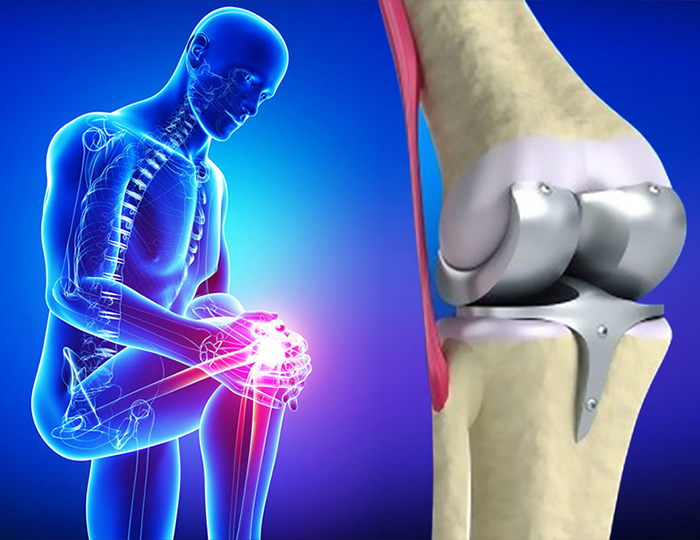

Diz Protezi (Total Diz Artroplastisi)

Diz protezi, diz eklemi yüzeylerinin hasar ettiği durumlarda uygulanan cerrahi tedavidir:

• İleri derecede diz osteoartriti

• Romatoid artrit

• Post-travmatik artroz

• Revizyon diz protezleri

• Unikondilar protezler (kısmi diz protezi)

Gelişmiş Diz Protezi Teknolojileri

• Kişiselleştirilmiş protezler

• Robotik destekli cerrahi

• Bilateral eş zamanlı protezler

• Yüksek fleksiyon protezleri